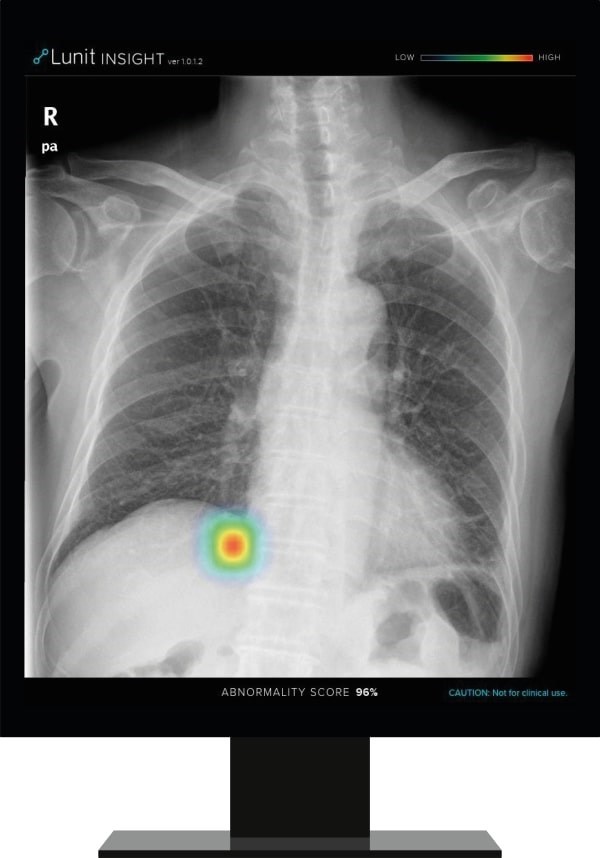

Lunit INSIGHT CXR detects findings and provides abnormality score on a chest X-ray image

Lunit INSIGHT CXR chest detection suite accurately detects 10 of the most common findings in a chest X-ray. The announcement is the latest extension of Philips' AI portfolio in precision diagnosis, which leverages this collaboration to achieve better patient outcomes, improve the experience of patients and staff, and lower the cost of care.

Lunit's AI software, Lunit INSIGHT CXR, is designed to provide accurate and instant analysis of chest X-ray images by mapping the location of the findings and displaying the scored calculation of its actual existence. It accurately detects 10 of the most common findings in a chest X-ray, prioritizes cases with abnormality scores, thereby allows fast triage of normal cases and enables radiologists to focus on reading abnormal cases. The algorithm performs at 97-99% accuracy rate, with its performance validated in major publications such as Radiology, JAMA Network Open, etc.